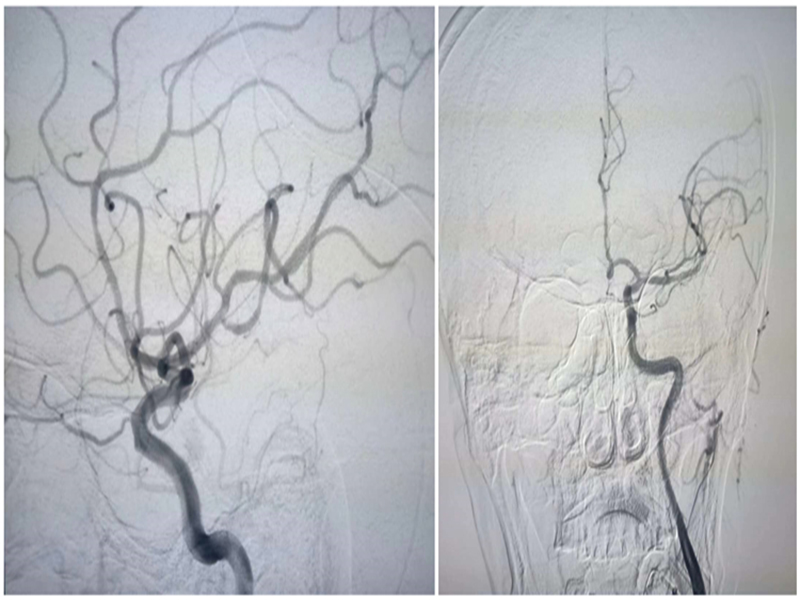

69 2 25 A1 MTICI 3